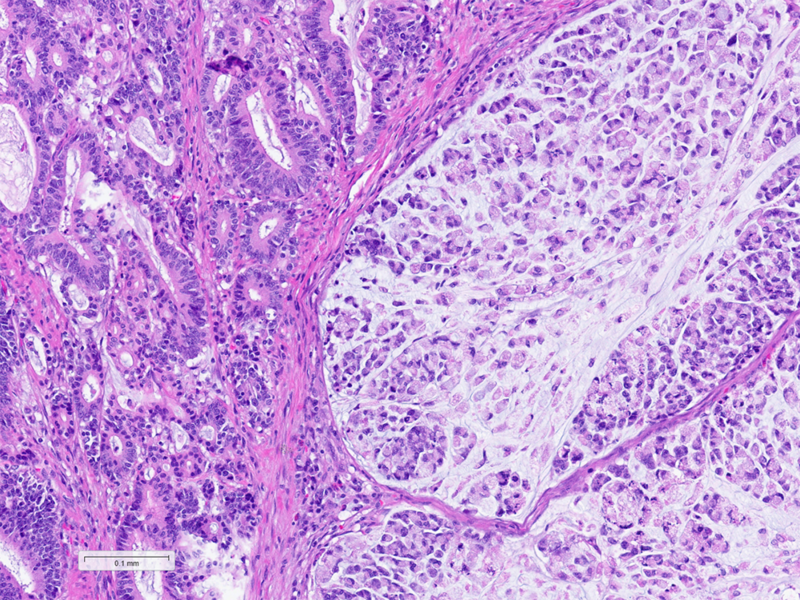

Histologically, the tumour was confirmed to be an adenocarcinoma invading through the gastric submucosa into the muscularis propria (Panel A), showing multiple architectural patterns. While the majority of the lesion displayed a tubular and papillary arrangement of neoplastic cells (Panel B), there were also mucin pools containing floating tumour cells (Panel C), as well as areas of discohesive signet-ring cells (Panel D), so called for their intracytoplasmic mucin droplet that eccentrically displaces the nucleus. The different architectural patterns were not entirely independent of each other nor were they intermingled, but rather arranged side by side (Panel E).